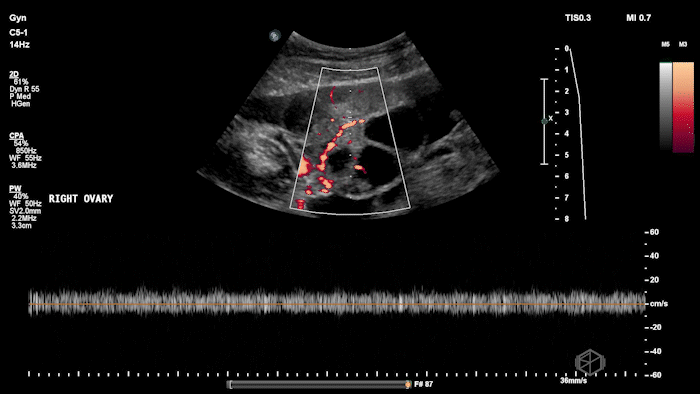

Dr. Nevias-Ida had a patient with 20’s female with PCOS who came in status post egg retrieval for IVF. The patient was complaining of abdominal pain, fullness, and nausea. She had some abdominal tenderness and distension.

She grabbed the probe, and working with Dr. Zimmerman, saw the following:

There is moderate free fluid, no obvious pleural effusions. The bilateral ovaries are enlarged with multiple cystic structures. There are normal arterial and venous waveforms for both ovaries.

Diagnosis: Ovarian Hyperstimulation Syndrome

• Typical ultrasound findings: enlarged ovaries with multiple cysts/follicles; free fluid (ascites) and in more severe cases pleural or pericardial effusions. (📚 PMID: 27998636)

• Preserved ovarian arterial and venous flow helps distinguish OHSS from acute ovarian torsion, where flow may be compromised.